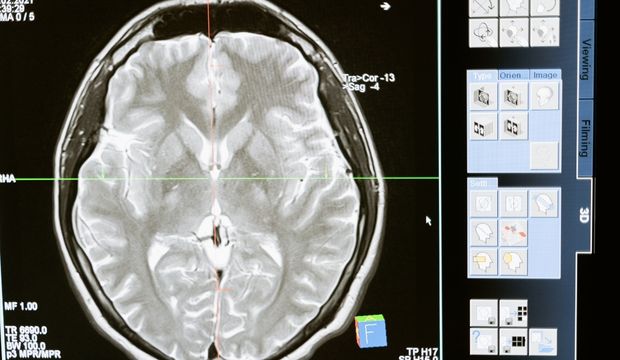

Brain research discovery

UTA Professor of Research Christos Papadelis and doctoral student Ludovica Corona have discovered how to identify which brain cells lead to epileptic episodes in children.